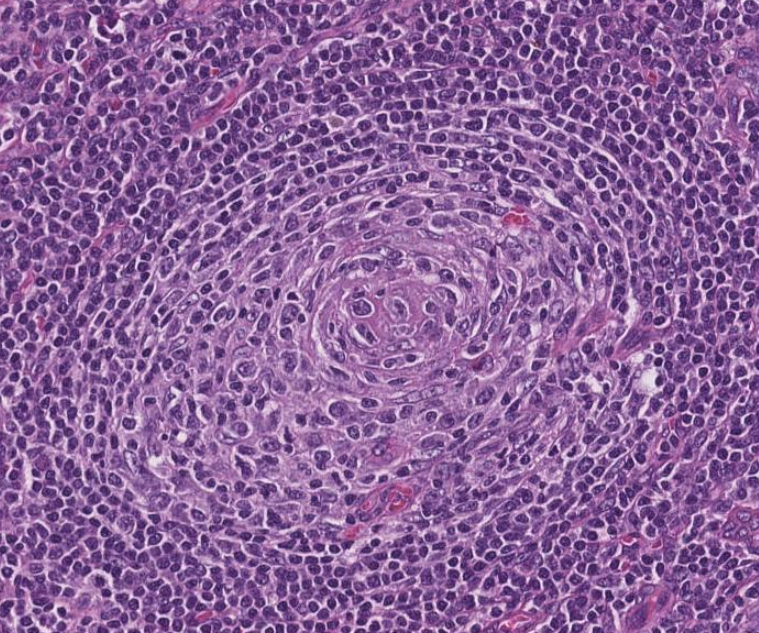

Illustration of a case of Follicular Lymphoma with Hyaline Vascular Unicentric Castleman Disease-"like" changes➡️

🩸Depleted germinal centers (Fig 2)

🩸Onion-skinning of mantle zones (Fig 2-3)

🩸Penetrating hyalinized vessels, imparting a lollipop-like configuration of germinal centers (Fig 3)

🩸Twinning (fusion) of follicles (Fig 4)

This case turned out to be postive for BCL2 translocation by FISH, with an aberrant CD10-positive population by flow cytometry analysis.

More on this variant of Follicular Lymphoma➡️pubmed.ncbi.nlm.nih.gov/28873356/

To complicate things, the "follicular variant" of Hyaline Vascular Unicentric Castleman Disease, with characteristic back-to-back follicular architecture, may greatly mimic follicular lymphoma as well ➡️pubmed.ncbi.nlm.nih.gov/8116226/

➡️pubmed.ncbi.nlm.nih.gov/19039195/

In summary, by morphologic examination, Follicular Lymphoma may present like Hyaline Vascular Unicentric Castleman Disease; Conversly, Hyaline Vascular Unicentric Castleman Disease may show a presentation very similar to Follicular Lymphoma